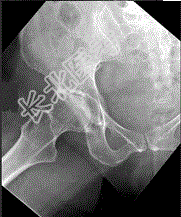

- 单项选择题女,67岁, 右髋和腹股沟痛6月余,结合图像, 最可能的诊断是